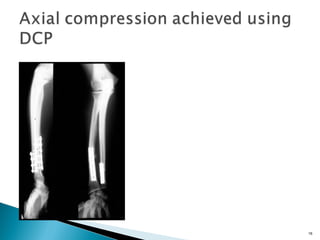

Compression plate:

eccentric DC (dynamic compression) hole

12 Compression plate: eccentric DC(dynamic compression) hole Removable device: compression device Interfragmentary compression by plate

14 Axial compression withremovable compression device Metaphysis: plate contoured but slightly less (shorter) than bone, bone is pulled towards plate Diaphysis: in order to compress Opposite cortex plate must be prebent